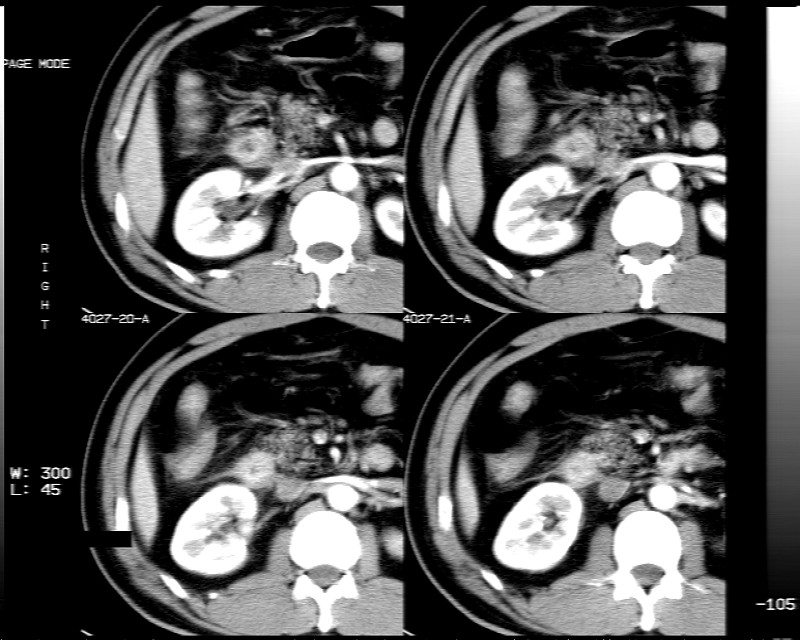

男性,52岁,腹痛,无发热,生化检查无明显异常,既往有胰腺炎病史,经治疗好转出院。

1)考虑肝左叶内侧段肝脓肿,不排除转移瘤。2)脂肪肝。3)慢性胆囊炎。4)十二指肠降部肿瘤可能。

胆囊炎、脂肪肝、肝脓肿。